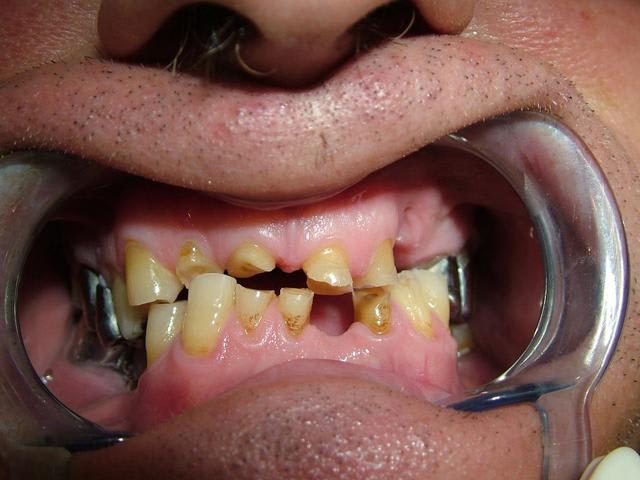

Homme de 57 ans avec DV effondrée.

Le patient n'a jamais porté de PAP.

Contrairement à ce qui a été dit...Il n'y a pas de perte de Dimension verticale. Les secteurs posterieurs sont plus ou moins preservés

Par contre dans le secteur anterieur l'usure des dents à été compensé par une egression qui donne l'illusion de perte de DV...

Le traitement est complexe car on peut pas vraiment augmenter la DV...il y pas ou peu de perte. Si on surevalue la DV, ça peut etre super mal toléré.

Oui...egressé et usée. Regarde l'os alveolaire de la pano.

De toute façon il n'y a pas perte de DV si il n'y a pas perte de calage posterieur...

L'idée de cingulum me semble la plus acceptable car il y a néanmoins un calage postérieur qui a sans doute permis de conserver la DV d'origine ou du moins éviter qu'il y ait un effondrement important. La remarque de cingulum me semble particulièrement pertinente.

Je confirme il y a un calage posterieur...presque pas de perte de DV. Donc la distance "maxillo-mandibulaire" n'a pas diminuée.

Il y a qu'a regarder la dimension verticale de repos...on saura si il y a variation de DV.

Merci pour toutes les réponses qui m'ont aidé à réfléchir au cas et surtout ne pas me précipiter sur mon plan de traitement stupidement. J'ai revu le patient il y a qq jours et je devais ce jour là lui faire la présentation du plan de traitement. Je lui ai expliqué que son cas était tellment complexe que je n'avais pas pour le moment de solution thérapeutique valable car je n'avais pas encore traité ce type de cas. Le patient a fort bien compris et j'en ai profité pour prendre des radios buccales ; en effet la mise sur occluseur que j'avais sur les précédentes photos était fausse. Le patient "occluse" différement. Voir les nouvelles photos jointes. Il y a très peu de contact antérieur ; j'ai bien demandé une dizaine de fois au patient de se mettre en occlusion pour arriver au même résultat que l'on voit sur les photos. Le patient a bien sur du mal à avoir un occlusion stable.

Ce qui m'interroge le plus c'est comment ce patient est arriver à user le bloc antérieur et arriver à cette situation. Il n'a pas d'habitudes nocives ( ex fumeur de pipes ou autres tics).

Il est vrai que la DV me semble conservé car il y a un calage postérieur côté droit et côté gauche.